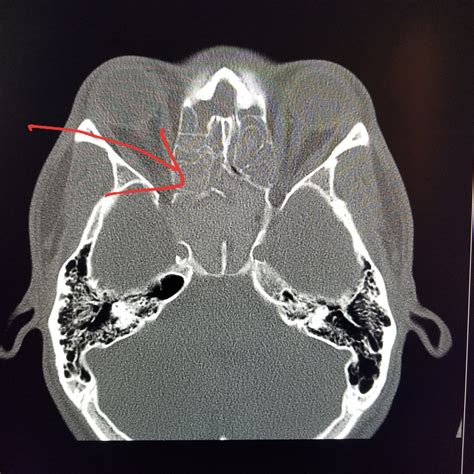

If you have been suffering from persistent sinus pressure, chronic congestion, or mysterious facial pain, your healthcare provider may recommend a Nasal CT scan to get a clearer picture of what is happening inside your nasal passages. This specialized imaging procedure is a cornerstone of modern otolaryngology, providing doctors with high-resolution, three-dimensional views of the complex structures within your nose and paranasal sinuses. Unlike a standard X-ray, which offers a two-dimensional look, a computed tomography (CT) scan provides detailed cross-sectional images, allowing specialists to pinpoint inflammation, structural abnormalities, or obstructions with remarkable accuracy.

A Nasal CT scan, often referred to as a sinus CT scan, is a non-invasive diagnostic tool that uses X-ray technology paired with advanced computer processing to create detailed images of your sinus cavities and nasal anatomy. When you undergo this scan, you will lie on a table that slides into a doughnut-shaped machine. The scanner rotates around your head, capturing multiple images from different angles to construct a comprehensive view of the area.

The primary purpose of this imaging is to assist ear, nose, and throat (ENT) specialists in diagnosing conditions that cannot be easily visualized during a routine physical examination. Because the sinuses are deep within the skull, traditional physical inspections only show a small portion of the nasal cavity. A CT scan, however, reveals the entire network of sinuses, highlighting potential issues that may require medical or surgical intervention.

• Trauma: Assessing facial fractures or damage to the nasal bones following an injury.

Interpreting the Results

Once the images are captured, a radiologist will review them and generate a report. They look for specific markers of health, such as clear, air-filled sinus cavities, versus signs of pathology, such as fluid accumulation, mucosal thickening, or bone erosion. Your ENT specialist will then combine these results with your clinical symptoms to make a definitive diagnosis.